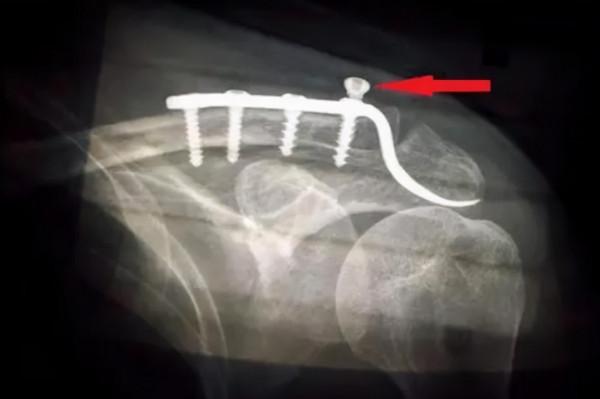

鋼板在身體內會發生斷裂嗎?

很多人認為鋼板在身體內是比較安全的,這樣可以為骨頭做支撐,其實鋼板也會出現斷裂,因為質量再好的東西用時間久了也會出現老舊身體內的鋼板,時間過久也可能會出現斷裂的現象,所以大家如果身體內長期植入鋼板建議定期複查,如果一旦感覺到鋼板斷裂,一定要及早處理,避免肉體上的痛苦。